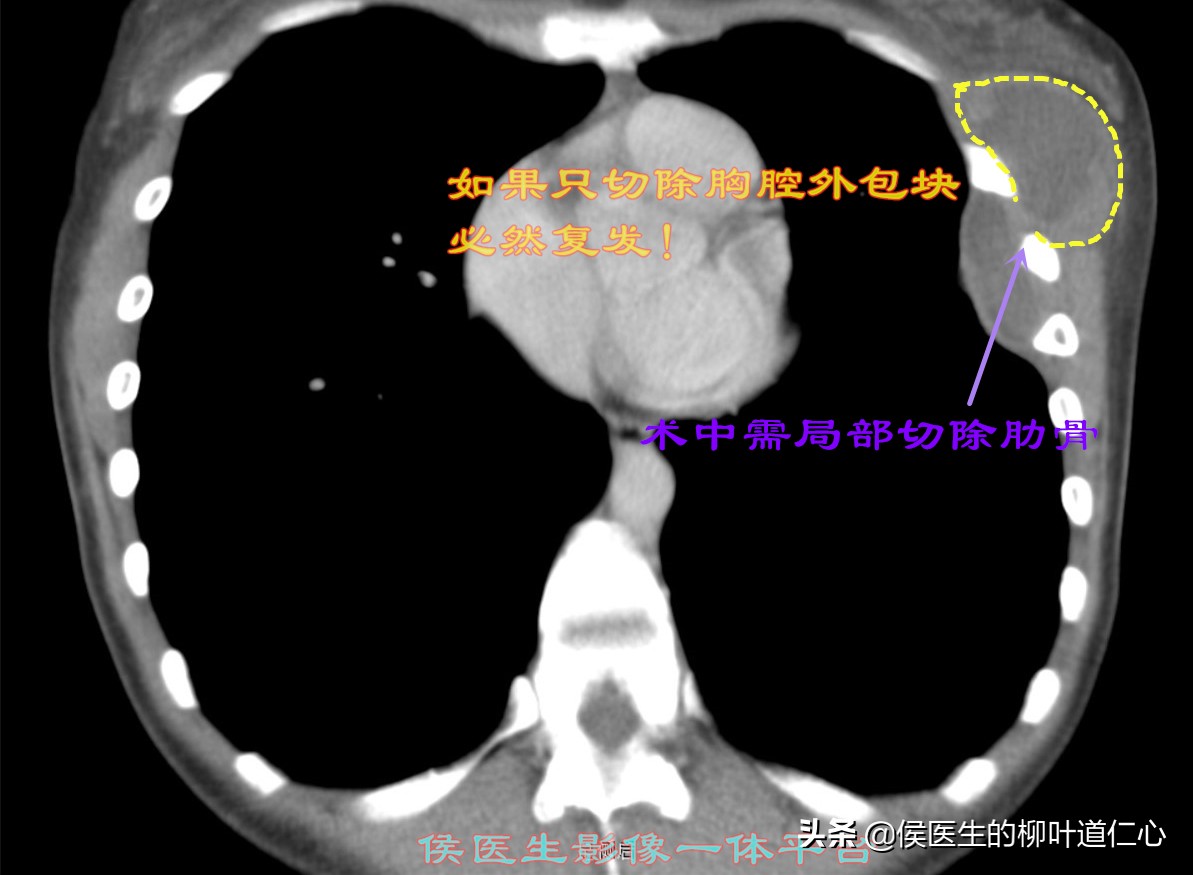

MPR重建,清晰地看到胸腔内外的结构如此相似,应该有着隐性的“通道”,如果仅仅处理胸壁病变,绝对的徒劳无功。

侯医生特地制作的动态影像,更能让您一目了然的理解,切除小段儿肋骨的必要性、清除胸腔内肺表面纤维板的重要性。

腋下纵行的小切口,完整切除了乳房下方包块并局部的肋骨、胸腔纤维板剥脱以及后胸壁小占位的切除......最小的创伤、最大的美容效果,最彻底地切除冲洗引流以及根据病理必要的术后治疗才是预防复发的关键......